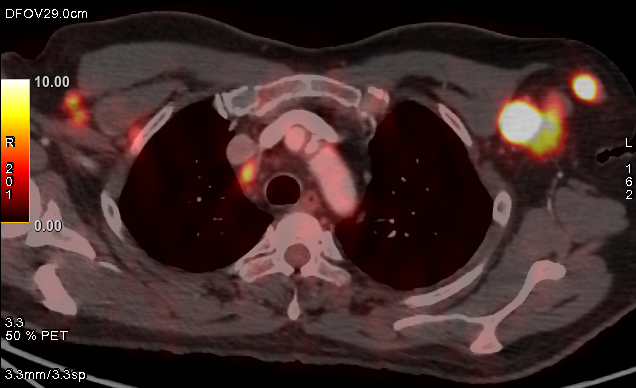

PET/CT:

Oncology

FDG PETCT whole body scan for cancer staging, restaging, response assessment, follow-up and guided biopsy